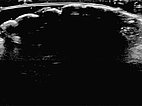

In sonography (B-scan), a total echo reflection with a pronounced acoustic shadow is found due to the high proportion of connective tissue on the surface of the nevus. The lesion itself cannot be visualized.

Color-coded duplex sonography also shows total echo reflection. No perfusion detectable even with a very sensitive setting for blood flow (6 cm/s).